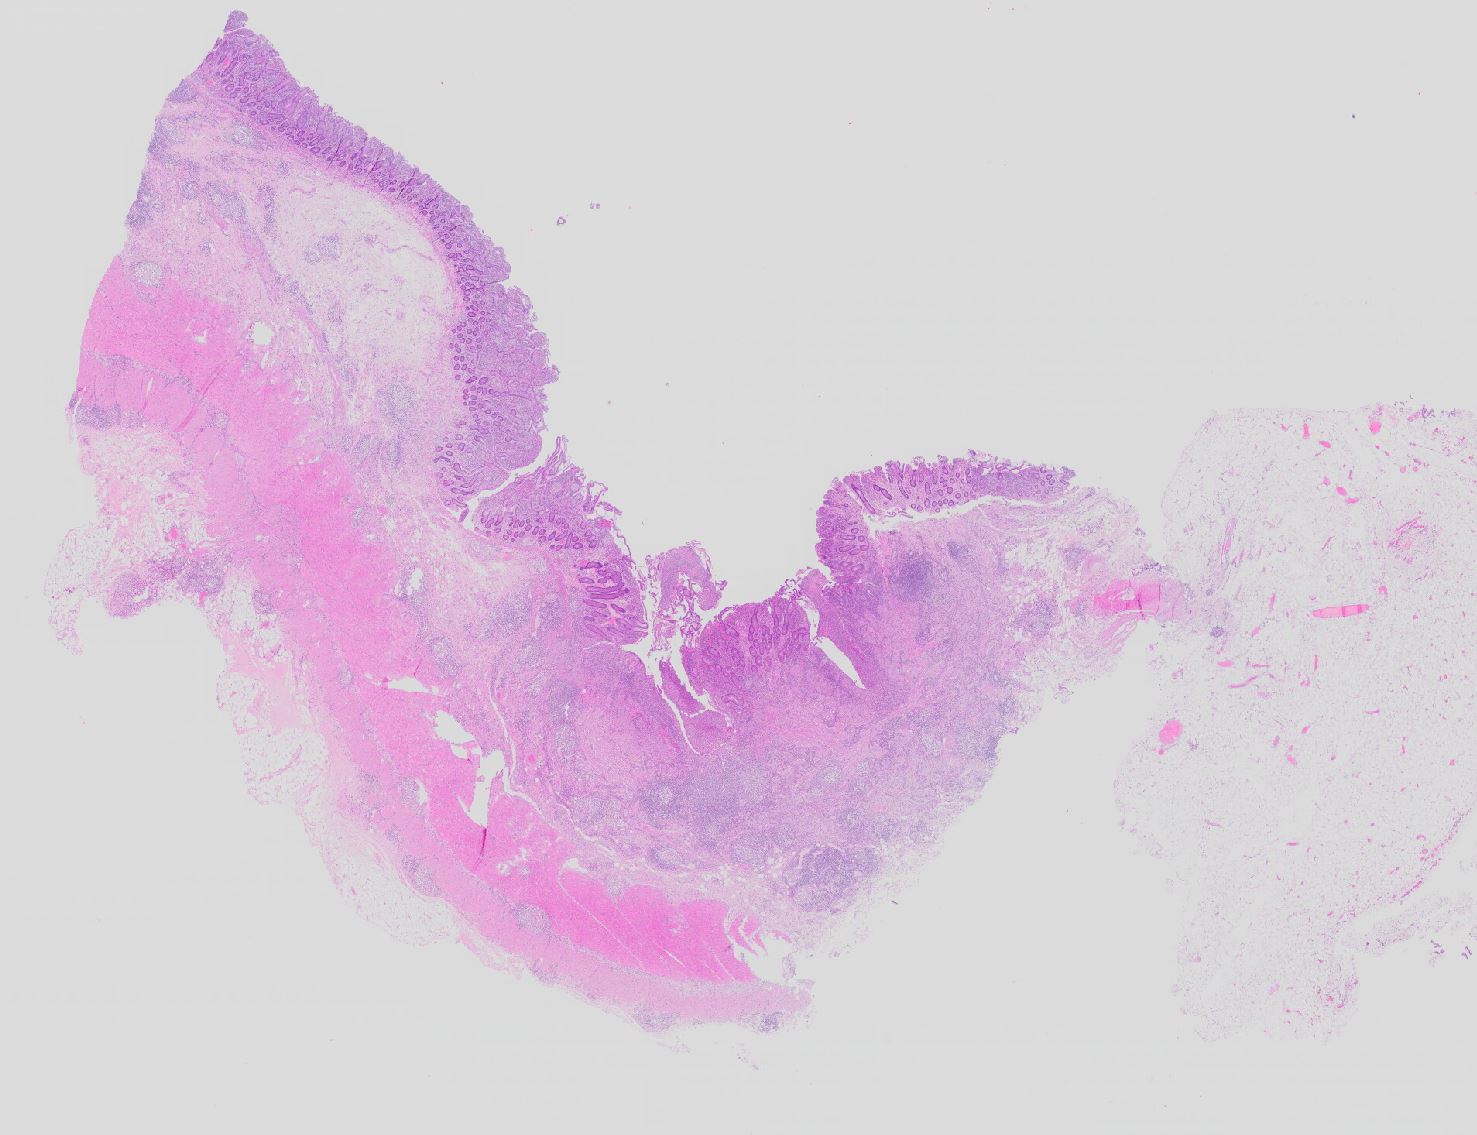

Basel 3BA HS/ Morbus Crohn

Morbus Crohn

Ileum terminal

Die Verteilung der Läsionen im Darm ist sowohl makrokopisch (> 2884) als auch mikroskopisch (> 656) (> 409) diskontinuierlich und herdförmig ausgeprägt. Im Gegensatz zur Colitis ulcerosa können beim Morbus Crohn nicht nur das Kolon, sondern sämtliche Abschnitte des Gastrointestinaltraktes befallen sein. Am häufigsten ist das terminale Ileum zusammen mit dem Kolon befallen.

Makroskopisch typisch sind oberflächliche aphthöse Ulzera, gartenschlauchartige Strikturen im Dünn- und Dickdarm mit segmental verdickter und fibrosierter Darmwand, intramurale Abszesse, entzündliche Konglomerattumoren und verbackene Darmschlingen mit Fistelbildungen. Häufiger im Dünndarm als im Dickdarm findet sich das klassiche Pflastersteinrelief der Schleimhaut aufgrund rissförmiger Ulzera zwischen ödematösen Schleimhautarealen (> 369) Granulationsgewebspolypen oder Pseudopolypen (erhaltene Schleimhautinseln in Ulkusarealen) (> 408) finden sich beim Crohn seltener als bei der Colitis ulcerosa.

In Biopsien der Darmschleimhaut zeigen sich als Zeichen der Chronizität eine Architekturstörung, reepithelialisierte Schleimhautdefekte und metaplastische Veränderungen. Typisch für den Morbus Crohn sind entzündlich veränderte Schleimhautabschnitte neben weitgehend normaler Schleimhaut. In der Lamina propria findet sich ein verdichtetes gemischtes Infiltrat bestehend aus Lymphozyten, Plasmazellen, Makrophagen, neutrophilen und eosinophilen Granulozyten. Typisch für chronisch entzündliche Darmerkrankungen ist eine basal betonte Lymphoplasmozytose der Lamina propria. Die neutrophilen Granulozyten finden sich herdförmig in der Lamina propria, im Kryptenepithel (Kryptitis) und als Ansammlung in dilatierten Krypten (Kryptenabszess). Erhaltene Schleimhautabschnitte zwischen ulzerierten Arealen und Granulationsgewebe imponieren als entzündliche Pseudopolypen.

Befunde in der Mukosa wie epitheloidzellige Granulome, aphthöse Ulzera und Erosionen und fokal aktive Entzündung sind nicht spezifisch für den Morbus Crohn. Jene histologischen Aspekte, welche die Erkrankung am besten charakterisieren, sind in der Darmwand gelegen und lassen sich an einer endoskopisch gewonnenen Biopsie nicht nachweisen (fissurale, spaltförmige Ulzera, submukosales Ödem mit Lymphangiektasien, submukosale Fibrose, transmurale Entzündung mit lymphoidzelligen Aggregaten, neuromuskuläre Hypertrophie mit Wandverdickung (> 364), subseröse und submuköse Granulome (> 1133)).

Morphologische Merkmale:

• Architekturstörung: Verplumpung und Abflachung der Dünndarmzotten. Verzweigte Krypten.

• Transmurale Entzündungsinfiltrate mit Lymphfollikelbildung.

• Zahlreiche epitheloid-riesenzellige Granulome in allen Wandschichten.

• Schlitzförmige fissurale Ulzera mit Vernarbung der umgebenden Submukosa.

• Verdichtetes lymphoplasmazelluläres Entzündungsinfiltrat in der Lamina proria.

Neutrophile Granulozyten in der Lamina propria (aktive Entzündung) und Gewebseosinophilie (vermehrte eosinophile Granulozyten in der Lamina propria).